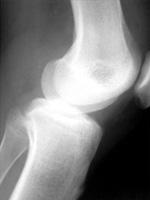

TraumatismoEs una de las especialidades más expuestas a los reclamos de mala praxis. El Dr. Ricardo Susman, Médico Especialista en Ortopedia y Traumatología, y Legista, explica en este artículo el contexto y los problemas que pueden surgir en el ejercicio de la profesión.

Defilippi Novoa definía a la ortopedia…”como la disciplina médica que estudia la corrección de las deformidades del esqueleto y el tratamiento de las enfermedades del aparato locomotor”… y a la traumatología como…”la rama de las ciencias médicas que estudia los traumatismos y sus secuelas”…

La Ortopedia y Traumatología es una especialidad eminentemente quirúrgica participando de todos los riesgos inherentes a la cirugía, a pesar que existen conductas clínicas, el predominio de la cirugía es evidente, por lo siempre estará latente la posibilidad de que ocurran accidentes, complicaciones o secuelas, que por lo común son ajenos al desempeño médico.

Es una especialidad de alto riesgo atento que ante los presuntos errores pueden verificarse alteraciones de la forma y/o de la función, situaciones que se ven y se perciben por el paciente y por lo tanto son potenciales generadoras de conflicto. Así también puede arribarse hasta la pérdida anatómica de un miembro.